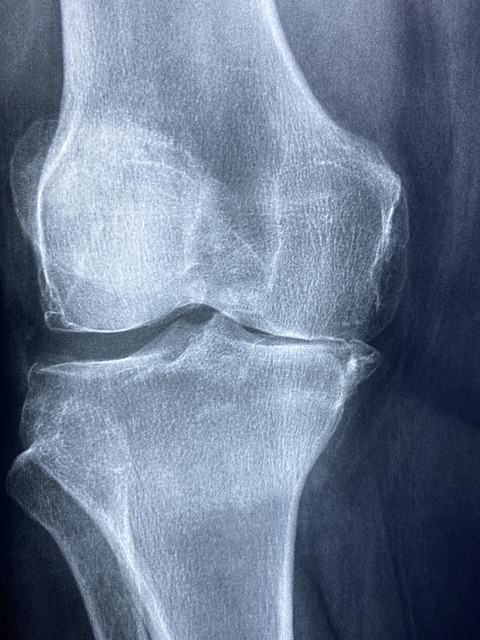

🔍 50대부터 무릎이 아픈 진짜 이유

관절에 일어나는 3가지 변화

1. 연골이 닳아 없어져요 😰

• 20대 대비 30-40% 감소

• 뼈와 뼈가 직접 마찰하면서 통증 발생